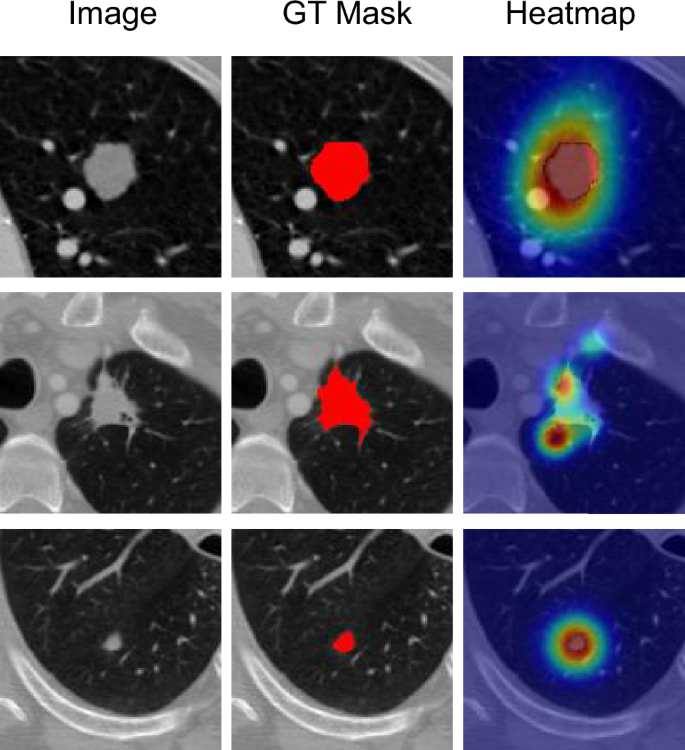

To better understand the model’s decision-making process and verify that it learns clinically relevant features, we visualized its internal attention mechanisms. As shown in the heatmaps in Fig. 5, the model demonstrates a strong ability to focus its computational resources precisely on the regions of interest. The high-activation areas (shown in red and yellow) closely align with the ground-truth nodule locations across various cases, including those with irregular shapes and subtle appearances. Notably, the model not only attends to the core of the nodule but also accurately highlights its boundaries and peripheral features, such as spiculation. This indicates that our model has learned to identify key diagnostic characteristics, providing a more interpretable and trustworthy segmentation result.

For each case (row), we show the original CT image, the ground-truth mask (GT Mask), and the corresponding attention heatmap. The heatmaps demonstrate that the model accurately focuses on the pulmonary nodule area, with heightened attention on the prominent features along the nodule’s boundary, validating its ability to capture clinically relevant information for segmentation.